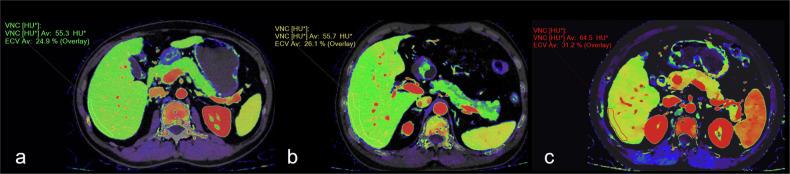

DLCT consists of a top layer sensitive to lower-energy photons and a bottom layer sensitive to higher-energy photons. This configuration enables simultaneous acquisition of two energy spectra from a single X-ray beam ensuring consistent spatial alignment and temporal resolution. Spectral raw images allow image post-processing to improve image quality, reduce radiation doses and contrast media doses, and generate multiple quantitative parameters. It has broad potential for early detection, accurate staging, efficacy assessment, and prognosis prediction of liver, pancreatic, and gastrointestinal diseases, as well as for the assessment of digestive system vasculature.

DLCT由对低能光子敏感的顶层和对高能光子敏感的底层组成。这种配置能够从单个X射线束同时采集两个能谱,确保空间对准和时间分辨率一致。光谱原始图像允许进行图像后处理,以提高图像质量、降低辐射剂量和造影剂剂量,并生成多个定量参数。它在肝脏、胰腺和胃肠道疾病的早期检测、准确分期、疗效评估和预后预测以及消化系统血管评估方面具有广阔的潜力。